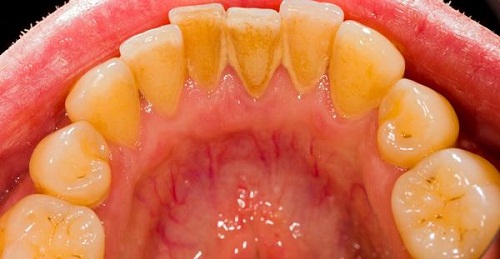

Có nhiều nguyên nhân dẫn đến việc hình thành cao răng nhưng về tổng quan thì do hằng ngày chúng ta sử dụng nhiều loại thức ăn khác nhau, do đó việc các loại đồ ăn thức uống còn thừa và sót lại ở răng, đến cuối ngày thì răng cần có nhu cầu được làm sạch để loại bỏ các chất thừa đó nhưng vì một lí do khách quan nào đó mà chúng ta không chú trọng đến công tác này. Lâu ngày, các thức ăn thừa này bám dính hình thành nên một lớp cao răng cứng cáp, bám chặt vào răng gây nên một số bệnh về răng miệng khá nguy hiểm, ảnh hưởng đến chất lượng cuộc sống và sức khỏe của người bệnh.

Lấy cao răng với đường nâu |